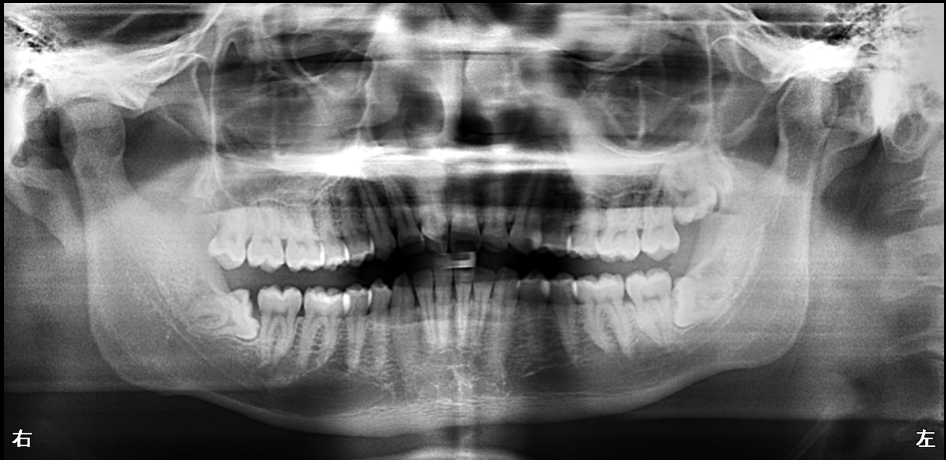

【50代男性】

インプラント・矯正・精密補綴で噛み合わせを再構築した症例

【全顎治療】

- 担当医

- 生野 誠

- 主訴

- 歯の治療をしたい

前歯がグラグラする

- 期間

- 4年

- 費用

- 450万円

- 治療内容

- 歯周病治療(HbA1c管理)

インプラント治療

精密根管治療

矯正治療

セラミックによる咬合治療

- 治療に伴うリスク

- 再感染